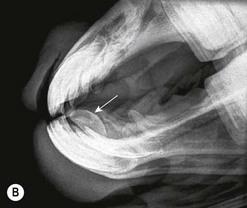

Fig. 13.20 (A) Intra-oral radiograph of a maxillary cheek teeth row.

image

(B) Intra-oral radiograph taken intra-operatively during a dental extraction procedure. A small bone-opacity fragment can be seen in the rostral aspect of the alveolus (arrow).

(Radiograph courtesy of W.H. Tremaine.)